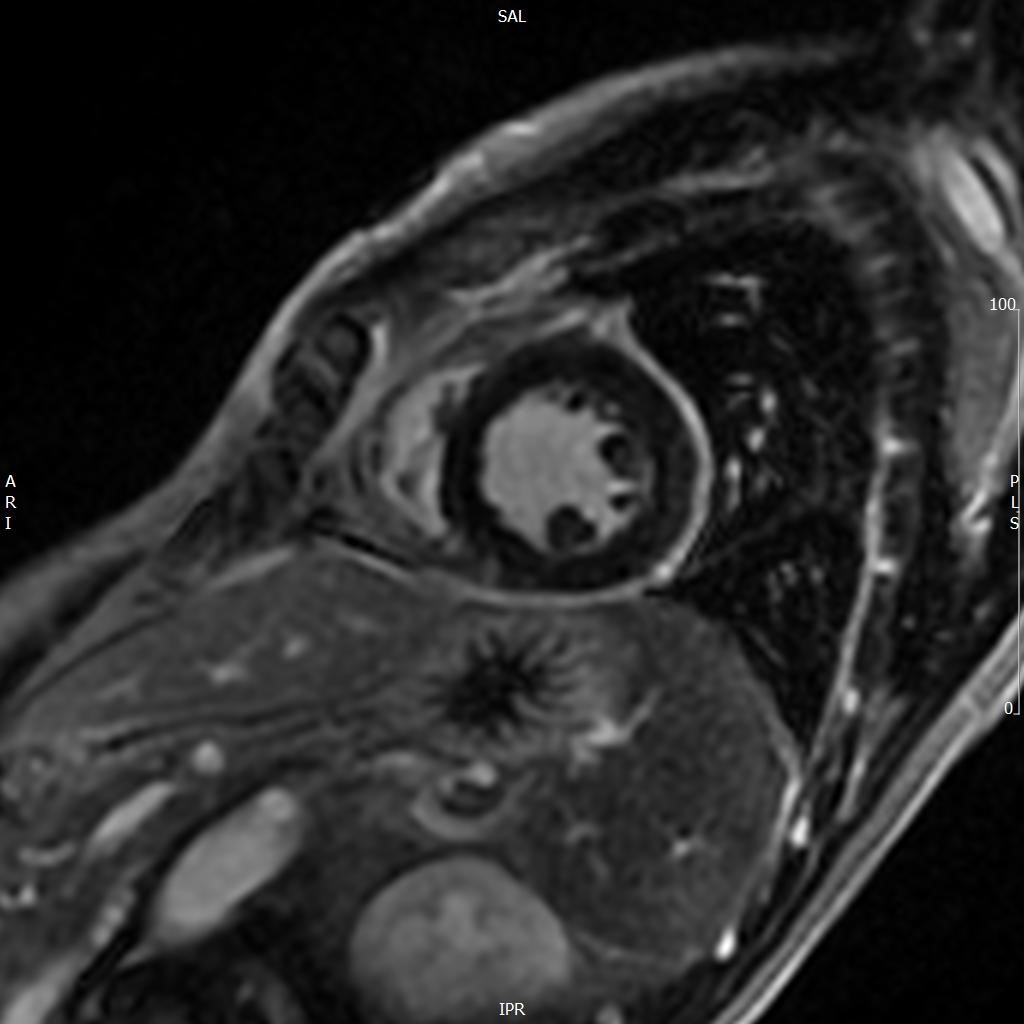

A 52-year old man with a history of diffuse large B cell lymphoma in remission presented with 3 weeks of shortness of breath, cough, fever, and shock. Electrocardiogram revealed sinus tachycardia, diffuse ST segment elevations, PR segment depression, prolonged QTc, and electrical alternans. Bedside echocardiogram was performed, revealing a large circumferential pericardial effusion with tamponade physiology. The patient underwent echo-guided pericardiocentesis with drainage of 400 ml of purulent fluid. Pericardial and blood cultures were positive for Haemophilus influenzae. A CT of the chest was indicative of empyema. Given the patient’s history of rituximab use, autologous stem cell transplant, and profound infection, immunoglobulin levels were drawn and found to be undetectable. The patient received 6 weeks of intravenous antibiotics with IVIG infusions. He was treated with colchicine and aspirin for purulent pericarditis. Two months later, a cardiac MRI was performed, which revealed resolution of the pericardial effusion. No evidence of constrictive pericarditis was noted on MRI, but continued pericardial enhancement was observed. Colchicine was continued for an additional 3 months. The patient made a full recovery at 6 month follow up.